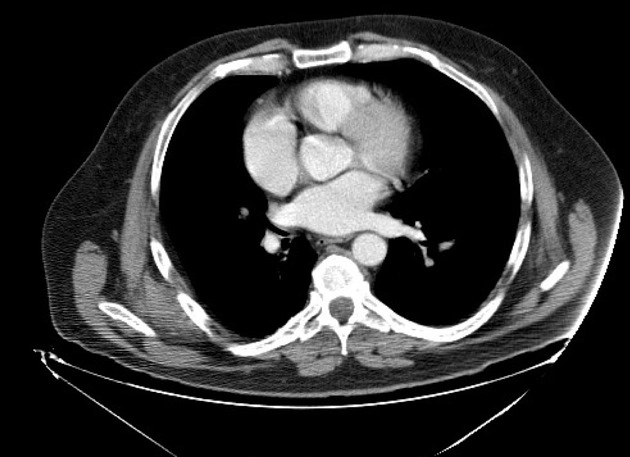

Tràn mủ màng phổi xuyên qua thành ngực (Empyema Necessitans)